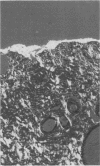

The performance of carbon and metallic inks, silver nitrate solution, and artists' pigments mounted in acetone was compared for marking the surface of surgical biopsy specimens. Using India ink is an unsatisfactory procedure because of slow drying, messiness, and spreading of the ink. It is concluded that use of artists' pigments has many advantages over other reagents, because of their rapid drying, resistance to tissue processing, and the ability to mark simultaneously many different planes of excision. Furthermore, the pigments are readily visible, are distinguishable from each other on microscopical examination, and the method entails little extra cost.